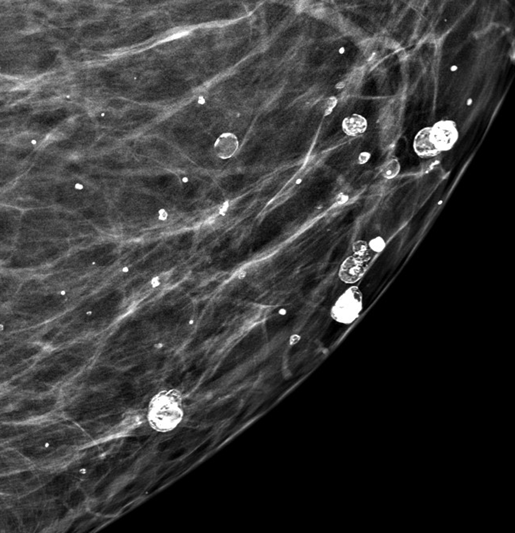

Кальцинаты в молочных железах чаще всего выявляются на маммографии. Они не вызывают боли и обычно являются случайной находкой. Большинство кальцинатов в молочных железах доброкачественные и связаны с возрастными изменениями, кистами, фиброаденомами, перенесенными воспалениями или травмами.

-2

Однако некоторые микрокальцинаты могут быть ранним признаком рака молочной железы, особенно если они:

• мелкие;

• неоднородные;

• имеют неровные контуры;

• сгруппированы в одном участке ткани.

В таких случаях требуется дообследование и, при необходимости, биопсия.